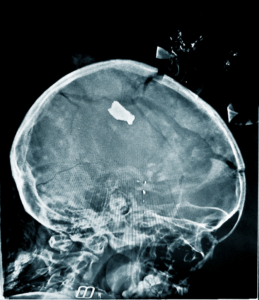

De dezembro de 2023 a dezembro de 2024, esta seleção de fotos apresenta os altos e baixos do trabalho médico-humanitário que fornecemos em mais de 70 países

Nos últimos 12 meses, as equipas da Médicos Sem Fronteiras (MSF) testemunharam a continuação e a escalada de conflitos, como em Gaza e no Sudão, onde se marcou o segundo ano de guerras ininterruptas.

Esta seleção de fotos, captadas no último ano, apresenta os altos e baixos do trabalho médico-humanitário que fornecemos em mais de 70 países.

A galeria mostra situações difíceis, mas também de resiliência e alegria, como o momento em que uma mãe vê a filha recém-nascida pela primeira vez, no Sudão do Sul. São fotos que mostram que o testemunho pode criar um ponto de conexão.

A nossa resposta médica proporciona alívio nas circunstâncias mais difíceis. Continuamos inspirados pela compromisso da nossa equipa e pela força interminável dos nossos pacientes, mesmo face a obstáculos cada vez maiores.